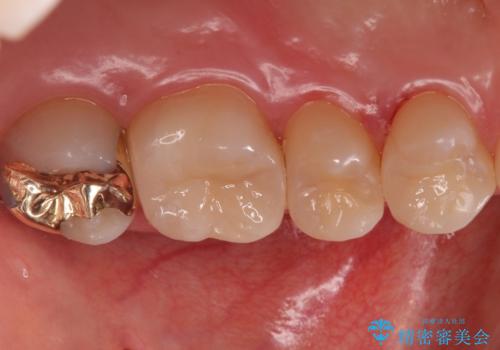

歯と歯の間の虫歯 インレーでの治療(セラミック・ゴールド)

- 銀歯のやり替えと虫歯の治療をご希望で来院された患者様です。

一番奥の歯は外から見えにくい部分であるためゴールドインレーで修復します。

その他はセラミックインレーで修復します。

- 左上46:セラミックインレー/77,000円×2 左上7:ゴールドインレー/77,000円×1費用は治療当時の料金となります